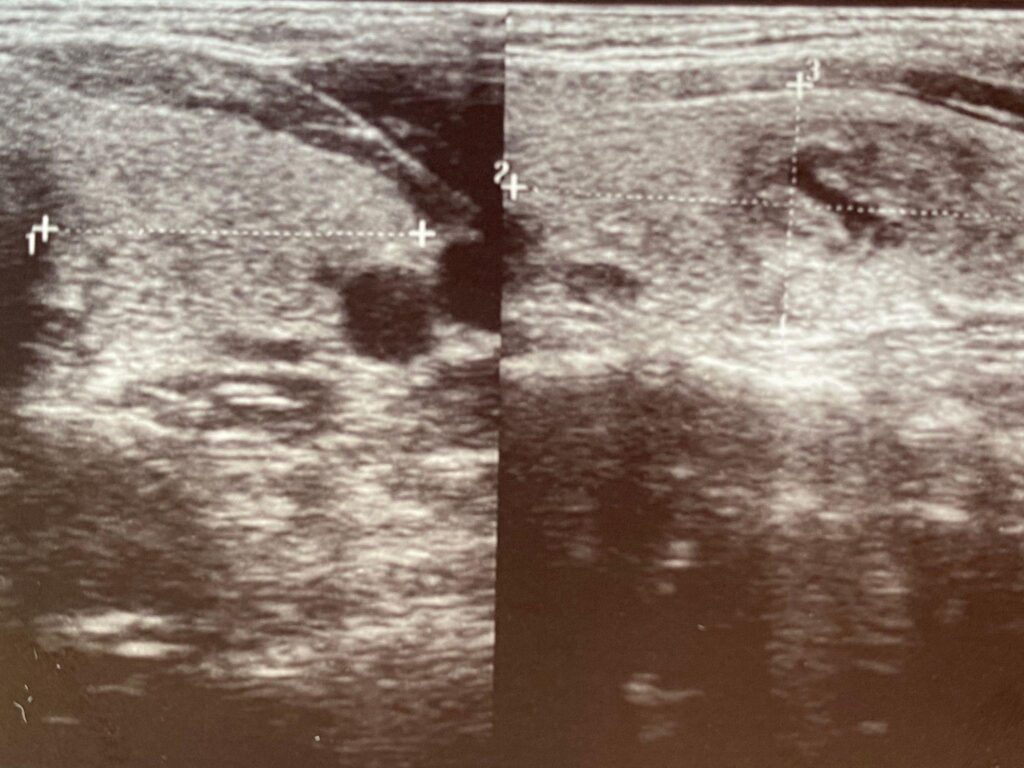

저도 조직검사 결과 갑상선 유두암 90% 의심소견을 받아서 수술적 치료를 받았습니다.

특히 여포암은 세침흡인검사(FNA)만으로는 확진이 어려운 경우가 많습니다. 피막 침범이나 혈관 침범은 수술 후 조직검사에서만 확인되는 경우가 흔합니다.

이 차이 때문에 영상 검사 전략도 달라집니다. 유두암은 경부 초음파 추적이 중요하고, 여포암은 폐 CT 등 추가 영상 검사가 고려될 수 있습니다.

유두암은 세포 핵 변화가 뚜렷하여 FNA 검사로 진단 정확도가 높습니다. 반면 여포성 종양은 양성과 악성을 세포 형태만으로 구별하기 어려워 ‘진단적 수술’이 필요한 경우가 존재합니다.